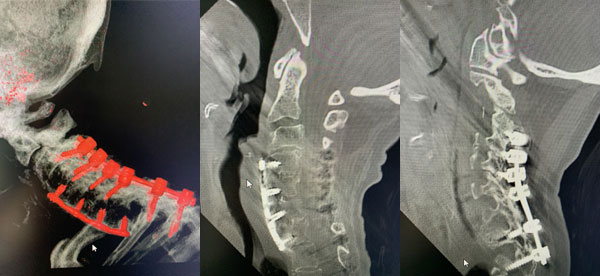

An MRI (Fig. 1) demonstrated severe stenosis at C2-3 with cord compression secondary to significant thickened posterior ligament and facet arthropathy. The patient had a posterior cervical laminectomy C1-3 to decompress the spinal cord and instrumented fusion C2-4.On exploration, the patient was deemed to be fused and the previous hardware was removed except for the lateral mass screws at C3 and C4 were left in. Postoperatively the patient had an uneventful course with some improvement in finger extensor strength.

Figure 1: Sagittal T2 MRI of the cervical spine demonstrates severe spinal cord compression at C2-3 above prior to instrumented decompression and fusion.